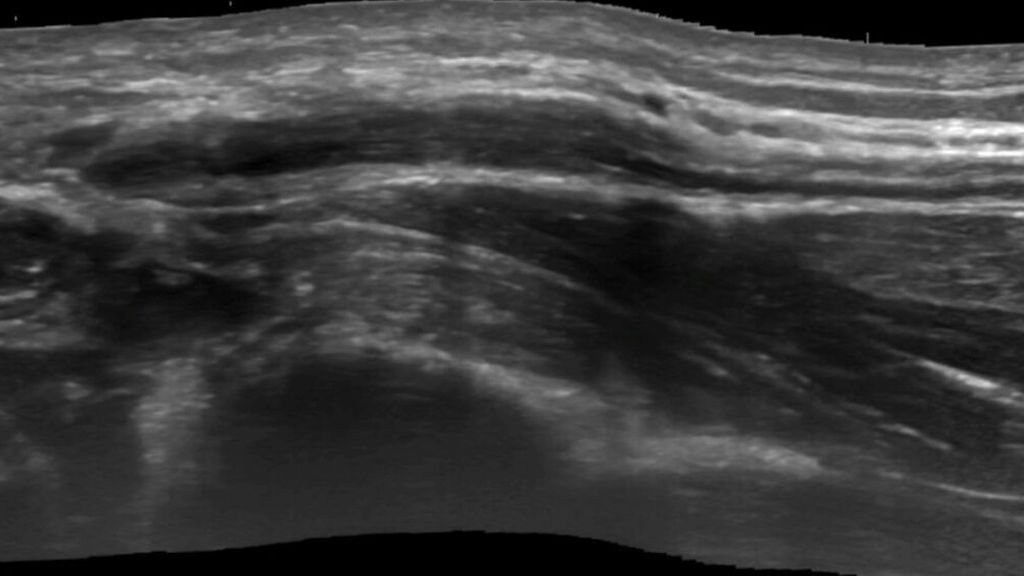

Die Elektrodiagnostik (NLG und EMG) hat in der klinischen Routine an den meisten Kliniken noch immer einen großen Stellenwert, obwohl sie in der Akutphase nur wenig zur Diagnostik und Therapieplanung beisteuern kann. Mithilfe der Elektrodiagnostik kann eine Neurapraxie (i.e. funktionelle Nervenschädigung, spontan und komplett reversibel) verlässlich von einer strukturellen Nervenschädigung unterschieden werden.9,18,19 Für die weitere Therapieplanung ist diese Information zwar ein guter Hinweis darauf, ob man zuwarten oder aber operativ tätig werden solle, allerdings ist sie für die detaillierte OP-Planung unzureichend. In den Händen eines erfahrenen Radiologen können mithilfe des hochauflösenden Ultraschalls (Abb.2) präzise Aussagen über den Zustand und die Pathologie des Nervs getroffen werden und so kann die Einleitung einer adäquaten Therapie ermöglicht werden.18

Der hochauflösende Ultraschall hat sich im Rahmen der Diagnose von Kompressionssyndromen, Nerventumoren und traumatischen Läsionen als verlässliches Instrument etabliert und kann in der Diagnose von iatrogenen Nervenläsionen genauere Hinweise auf Vernarbungen, Hämatome, Lokalisation, Lagebeziehungen (z.B. zu Osteosyntheseplatten) und Zustand des Nervs (z.B. Schwellung) geben.9,18,19

Der große Vorteil der Ultraschalldiagnostik liegt in der Tatsache, dass es sich um ein dynamisches Verfahren (im Gegensatz zur MRT) handelt. Weiters ermöglicht der hochauflösende Ultraschall exakt gezielte Nervenblockaden. Diese sind sowohl in der Diagnostik als auch in der Therapieplanung von großer Bedeutung.